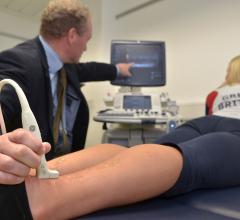

The Olympic Games give elite athletes a chance at athletic triumph, but also carry a risk of injury. When injuries occur, it is critical that they be evaluated quickly. Onsite imaging services play an important role in the management of Olympic athletes with sports-related injuries and disorders, according to a new study published online in the journal Radiology.

At this year’s European Congress of Radiology (ECR), Feb. 28-March 4 in Vienna, Austria, ContextVision will showcase two new products: VolarView for handheld ultrasound devices and the Orthopedic Package for radiography. ContextVision will also hold demonstrations of its imaging enhancement software for 2-D/3-D/4-D ultrasound, X-ray, magnetic resonance imaging (MRI) and mammography for booth visitors.